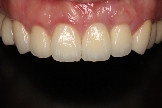

病患治療後,最終假牙完成照。

病患恢復自信的笑容。